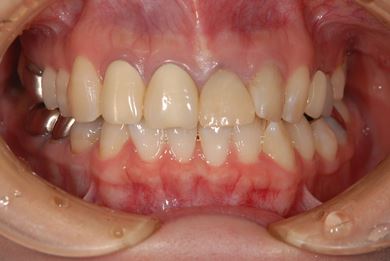

| 性別/年齢 | 女性 / 27歳 | ||||||||||||||||||||||||||||||||

| 主訴 | 審美歯科治療を希望。歯ならびもできるかぎりそろえたい。 | ||||||||||||||||||||||||||||||||

| 治療内容 | オールセラミック4本(オールセラミック用土台4本)、メタルボンドセラミック2本(メタルボンドセラミック用土台2本) | ||||||||||||||||||||||||||||||||

| 総治療費 | 867,825円 | ||||||||||||||||||||||||||||||||

| 治療期間 | 5ヶ月 |